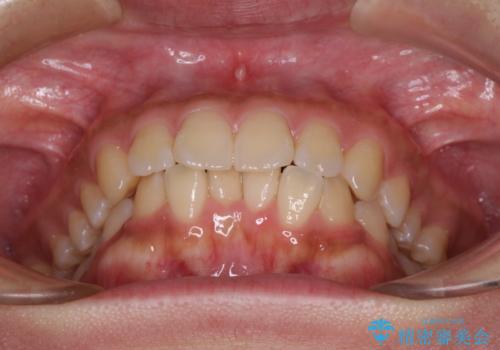

- 前歯の突出感を気にして来院された患者様です。

咬合力が非常に強く、咬合力で前歯が前方に押し広げられており、上下唇に閉じにくさが認められました。

上下左右の第一小臼歯4本を抜歯し、ワイヤー装置にて矯正治療を行うこととしました。

強い咬合力により前歯の隙間がなかなか閉じられず、治療期間は長いものとなりましたが、横顔の印象が大きく変わるほど口元の印象を改善することができました。